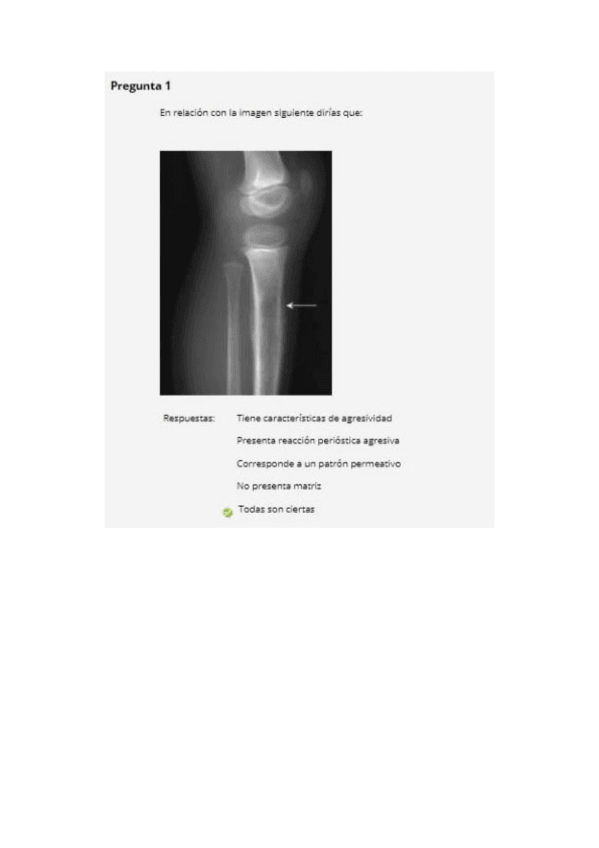

examenes rayos

He publicado nuevos examenes de 3º radiología clínica y diagnóstico por la imagen: examenes rayos

Examen-rayos-2016-2017-2.pdf

Todos-examenes-hasta-2020.pdf

Examen-rayos-2017-2018.pdf

Examen-rayos-2015-2016.pdf

Examen-rayos-2021.pdf

Examen-rayos-2016-2017.pdf